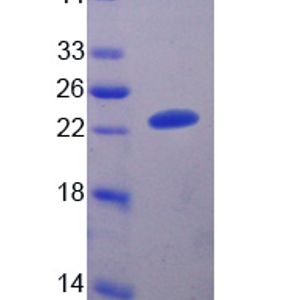

APR 21, 2020ImmunologyApril 17, 2020, Sino Biological announced this week that the company launched the world’s first coronavirus antige ...